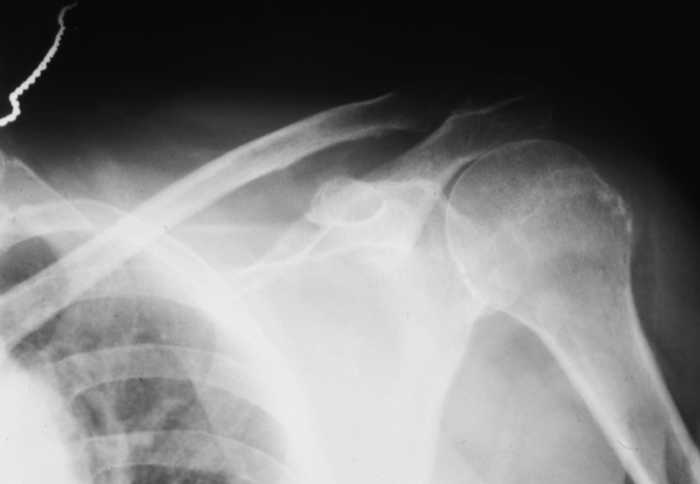

Radiology MS 29 - Normal Shoulder

Identify: Clavical, Acromion, Coracoid Process, Glenoid, Humeral Head